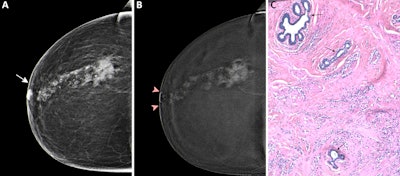

Preoperative CEM images in a 73-year-old female patient show true-positive findings of a nonluminal ERBB2-positive (formerly HER2 or HER2/neu) grade 3 invasive carcinoma of no specific type, with a spiculated mass with high conspicuity heterogeneous mass enhancement in the posterior third of the right upper outer quadrant. An area of high conspicuity clumped nonmass enhancement with associated microcalcifications (craniocaudal view of low-energy images in A; craniocaudal view of recombined images in B) extended from the mass to the nipple-areolar complex (minimum enhancement-to-nipple distance on the craniocaudal view, 0 mm), which on a (C) photomicrograph (hematoxylin-eosin stain at ×50 magnification) was completely infiltrated by malignant epithelial cells with diffuse desmoplastic stromal reaction, consistent with tumor involvement. Three residual normal ducts (arrows in C) were still present. Aside from the continuity of the nonmass enhancement with the nipple-areolar complex, other findings at CEM that were consistent with pathologic nipple involvement were the presence of an inverted nipple type and of nipple retraction (A, B), periareolar skin thickening (arrow in A), and disruption of the superficial linear enhancement (arrowheads in B).RSNA